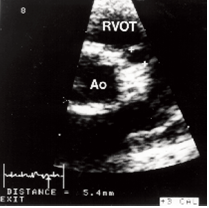

Aneurysmata kunnen bij 20-25% van de kinderen met de ziekte van Kawasaki vastgesteld worden. Dat gebeurt met behulp van een ‘echo’ van het hart (echocardiografie), een zeer precies een uiterst kindvriendelijke techniek. Indien de ziekte vroegtijdig herkend en behandeld wordt, kan het risico op aneurysmata van de kransslagaders verlaagd worden tot <10%. Daarom is het van belang de ziekte van Kawasaki snel te onderkennen en te behandelen.

Patiënten kunnen zich aanmelden voor een poliklinische controle in het AMC. Dit geldt zowel voor kinderen uit Amsterdam en omstreken, als voor patiënten uit andere centra. Het betekent in de regel dat uw kind 6 tot 9 maanden na het begin van de ziekte opgeroepen zal worden. Allereerst is deze controle bedoeld om contact te hebben met ouders en patiënten, zodat zij hier terecht kunnen met al hun vragen. Daarnaast wordt er bloedonderzoek gedaan en meestal ook een echo van het hart gemaakt.

Sinds 2015 wordt een CT-scan van de kransslagaders gemaakt met een zeer lage-dosis röntgenstraling. Zo wordt de stralenbelasting tot een minimum beperkt en kunnen we toch de precieze afmetingen en het gehele beloop van de vaten van het hart te kunnen beoordelen, hetgeen met echocardiografie niet volledig kan. Indien nodig, doen we dit snelle onderzoek kort na het doormaken van de acute fase van de ziekte, maar meestal proberen we ook daarbij – indien de verdenking op ernstige schade niet hoog is – om dit onderzoek pas op latere leeftijd te verrichten.

In het AMC worden sinds 2007 MRI’s van het hart gemaakt. Magnetische Resonantie Imaging (MRI) is een beeldvormingsmethode die meer nog dan de vaatstructuur zelf, juist de knijpkracht en doorbloeding van het hart gedetailleerd in beeld kan brengen. Het MRI-onderzoek is een niet invasief onderzoek, geheel vrij van röntgenstralen, dat geheel veilig is voor uw kind maar wel langer duurt. Dit onderzoek is bedoeld om eventuele restschade (n.a.v. een aneurysma) aan de hartspier zelf na het doormaken van de ziekte van Kawasaki in beeld te brengen. Dit onderzoek wordt meestal gedaan vanaf de leeftijd 12 - 14 jaar.